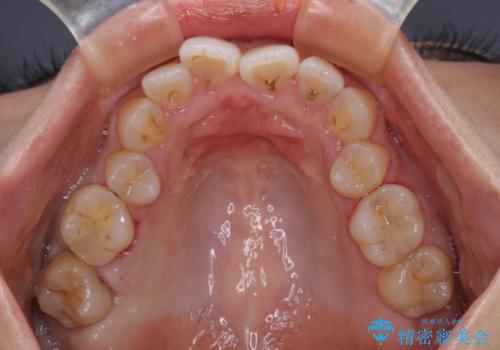

前歯のデコボコを改善 インビザラインの矯正治療

- 前歯のデコボコを治したいとのことで来院された患者様です。

上下顎ともに歯列全体の後方移動とIPR(歯と歯の間を削る)によってデコボコが解消するように設計し、インビザラインにより治療を行うこととしました。

下顎前歯は後戻りを起こしやすいため、舌側を細いワイヤーで固定し、マウスピース型リテーナーで保定を行うこととしました。